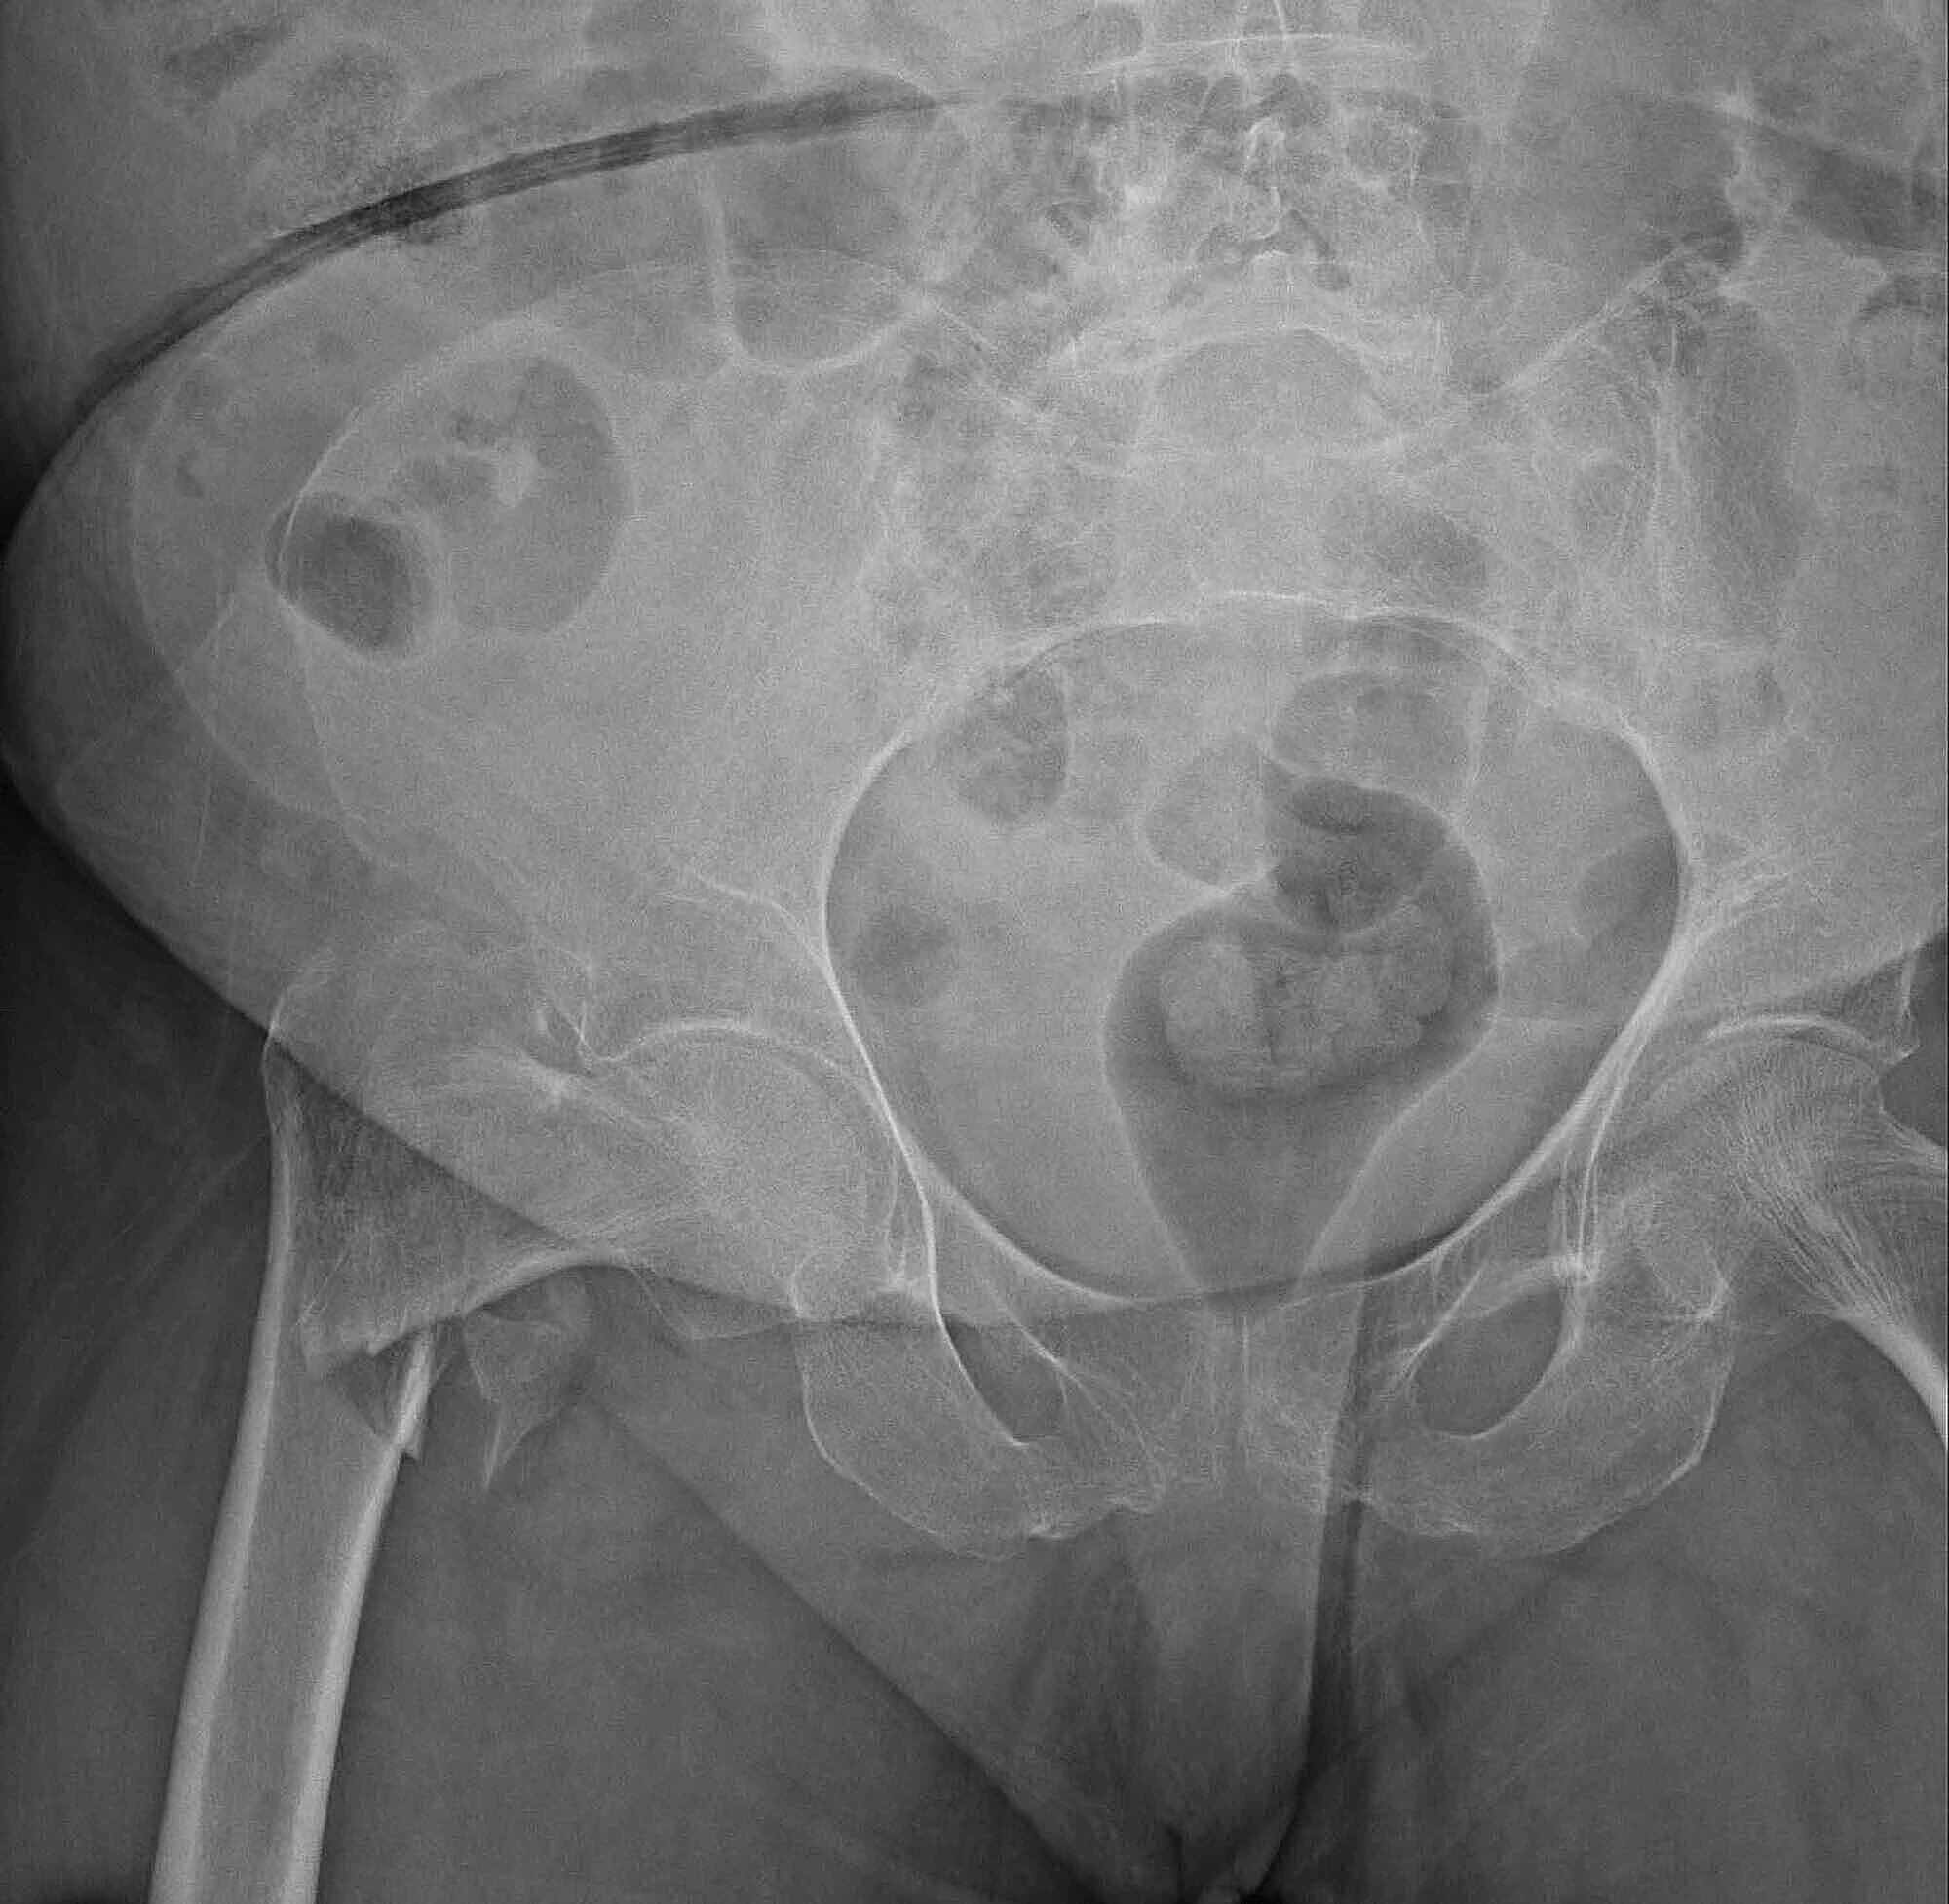

An adequate classification of proximal femur fractures from Xray images is crucial for the treatment choice and the patients' clinical outcome We rely on the commonly used AO system, which describes a hierarchical knowledge tree classifying the images into types and subtypes according to the fracture's location and complexity In this paper, we propose a methodThere are a number of classification systems for intracapsular fractures of the proximal femur, but none has been shown to be practical with satisfactory reproducibility and accurate predictive value We have investigated the AO classification and evaluated intra and interobserver accuracy and its value in predicting treatment and outcomeClassification General Principles 1 Humerus 2 Radius/Ulna 3 Femur 4 Tibia/Fibula1,2,3 = Proximal, diaphysis, distal Diaphysis/Epiphysis A Simple extraarticicular (1spiral, 2oblique, 3transverse) B Segmental partialarticular C Comminuted articular Explanation The AO group has developed a comprehensive classification of

Fractures of the proximal femur are divided into three groups Type 31A extraarticular fracture, trochanteric area Type 31B extraarticular fracture, neck Type 31C articular fracture, head For the purpose of discussion in this chapter, subtrochanteric fractures are also included (Müller AO Classification 32A, B, or C) as the same principles and techniquesAO Surgery Reference—Dog Procedural descriptions of fracture treatment, diagnosis and indications for the most common injuries in dogs CMF, proximal femur, distal femur, patella, tibial shaft (members only) Femoral shaft (free module) Access all dog modules hereBackground Radiographic fracture classification helps with research on prognosis and treatment AO/OTA classification into fracture type has shown to be reliable, but further classification of fractures into subgroups reduces the interobserver agreement and takes a considerable amount of practice and experience in order to master

LCP Proximal Femoral Hook Plate System The LCP Proximal Femoral Hook Plate System has many similarities to traditional plate fixation methods, with a few important improvements The technical innovation of locking screws provides the ability to create a fixedangle construct while using familiar AO plating techniques Locking capabil 2 Materials and methods 21 AO/OTA Proximal Femur Classification The proximal femur is labelled as "31", being the first number related to the femur and the second to the proximal region Then the intertrochanteric region is coded as "A", the neck of femur "B" and the femoral head as "C"